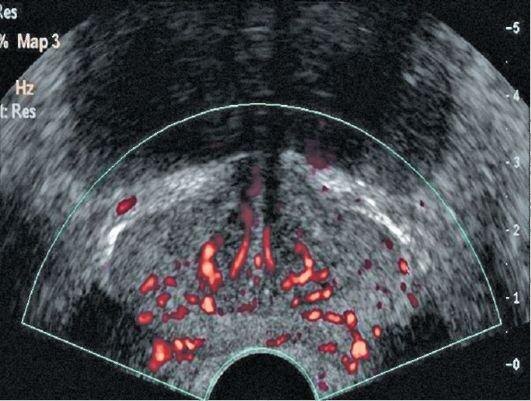

Рак простаты, к которому всегда приводит простатит – вопрос лишь времени

Рак простаты, вышедший за пределы предстательной железы и поразивший близ расположенные ткани.